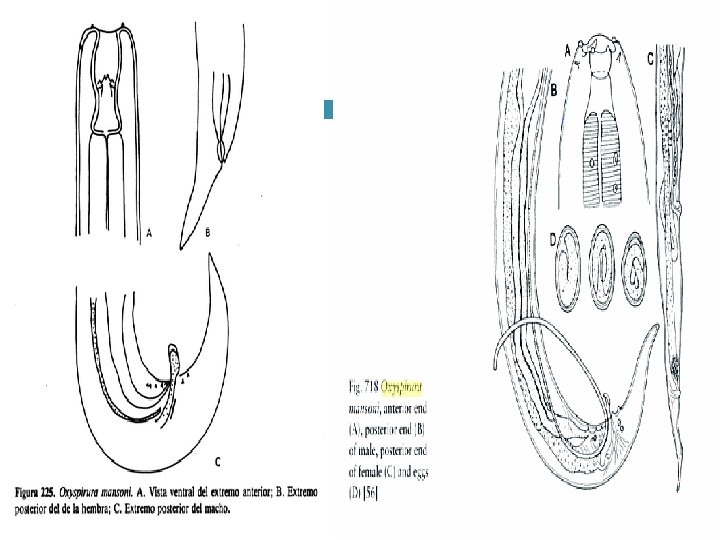

Etiologia: Oxyspirura mansoni Oxyspirura parvorum Oxyspirura petrowi

Localizacion: • Membrana nictitante • Conducto nasolagrima l • Sacos conjuntivos

Patogenia: A. Irritativa A. Inflamatori a A. Traumati ca